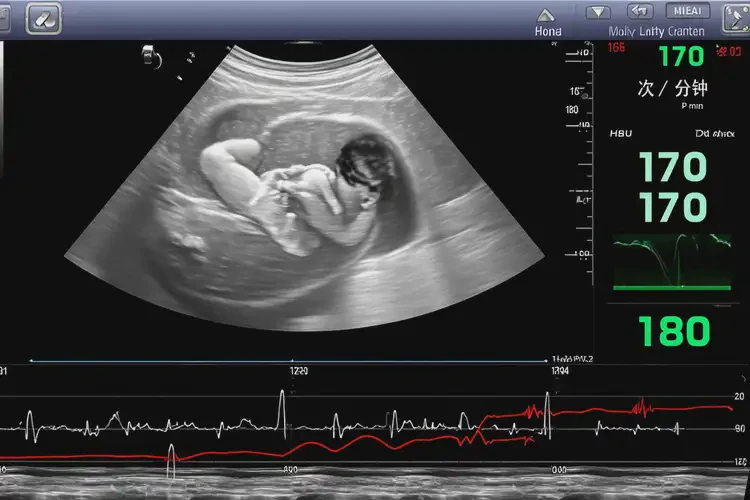

孕22周1天胎心率170多還要保胎嗎

胎心率170次/分鐘在孕22周1天屬于正常范圍,通常無需特殊保胎措施。

胎心率是指胎兒心臟每分鐘跳動的次數(shù),是評估胎兒健康狀況的重要指標(biāo)之一。在孕22周1天,胎兒的胎心率通常在120-160次/分鐘之間被認(rèn)為是正常范圍。胎心率偶爾超過這個范圍并不一定意味著存在問題。以下是關(guān)于胎心率和保胎的詳細(xì)信息:

孕22周1天胎心率170多還要保胎嗎(圖1)